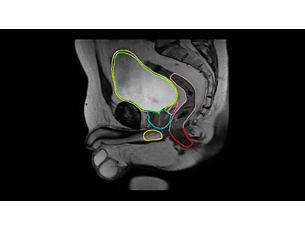

With its excellent soft-tissue contrast, MRI offers excellent visualization of tumor boundaries and proximity to nearby critical structures – a key factor for more confident delineation and improved treatment plans. What’s more, MRI’s advanced imaging capabilities provide you with a ‘toolbox’ to design personalize treatment options for each patient. - Be confident in image quality

With its excellent soft-tissue contrast, MRI offers excellent visualization of tumor boundaries and proximity to nearby critical structures – a key factor for more confident delineation and improved treatment plans. What’s more, MRI’s advanced imaging capabilities provide you with a ‘toolbox’ to design personalize treatment options for each patient. - Be confident in image quality

Our innovative MRCAT (MR for Calculating ATtenuation) clinical applications lets you plan radiation therapy using MRI as primary imaging modality. Within just one, fast MR exam, MRCAT provides both excellent soft-tissue contrast for target and OAR delineation and CT-like density information for dose calculations. This not only extends the benefits of MRI’s excellent soft-tissue contrast to radiotherapy planning, but it also eliminates arduous, error-prone CT-MRI registration from the process, reducing uncertainties and complexity.

MRCAT Pelvis lets you plan radiation therapy using MRI as a single modality solution. Within just one MR exam, MRCAT Pelvis provides excellent soft-tissue contrast for target and OAR delineation, and continuous Hounsfield units for dose calculations. MRCAT (MR for Calculating ATtenuation) data can be used for export to treatment planning systems for CT-equivalent** dose calculations. In addition, MR-based imaging enables CBCT-based positioning based on soft-tissue contrast with the look and feel of CT.